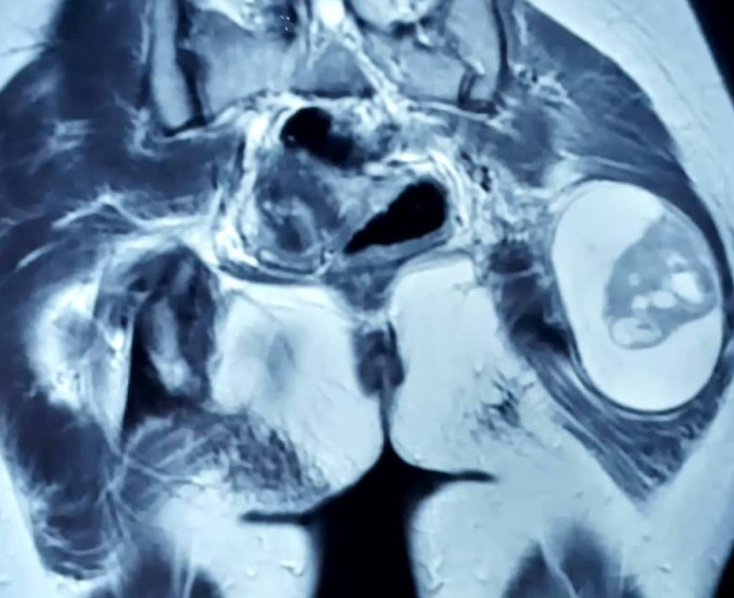

Clinically, a 5x5 cm, mobile mass was noted in the left gluteal region, in the muscular plane. Her left lower limb power was ⅘, tone was normal, and sensations were intact. There were no signs of vascular deficit. Her biochemical and hematological parameters were normal. She was evaluated with an MRI of the hips including the left lower limb, which revealed - a well-defined, soft tissue density lesion measuring 5x6x5.9 cm, in the intermuscular plane of the left gluteal region (Figure 1). It was in close relation to the neurovascular bundle, showing altered signal intensity. Similar lesions were noted of size 3.4x3.5x4.9 cm and 2.8x3.5x3.9 cm in the mid-thigh region (Figure 2) - s/o multiple nerve sheath tumors in the left gluteal and intramuscular plane of the left thigh region. Core needle biopsy from the gluteal mass reported benign spindle cell neoplasm, with possibility of neurogenic origin.

Figure 2. Soft tissue density lesions of size 3.4x3.5x4.9 cm and 2.8x3.5x3.9 cm, in the mid-thigh region.